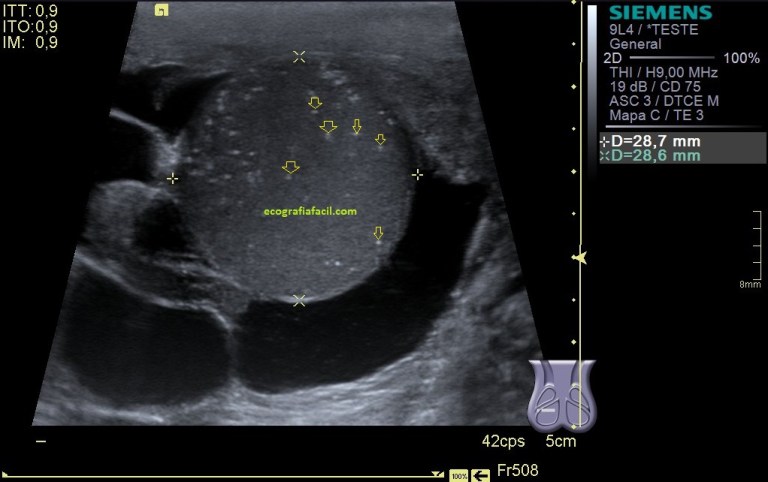

En el final del protocolo tenemos el infraespinoso. En relación con este corte te voy a contar que es un corte donde estudiamos en normalidad, articulación glenohumeral, labrum posterior (triangular e hiperecogénico), músculo infraespinoso como puedes ver en las dos imágenes siguientes, donde existe normalidad en la primera y donde coexiste la anatomía con la patología por la ausencia del labrum, sustituido por una buena cantidad de líquido justo en la articulación glenohumeral.